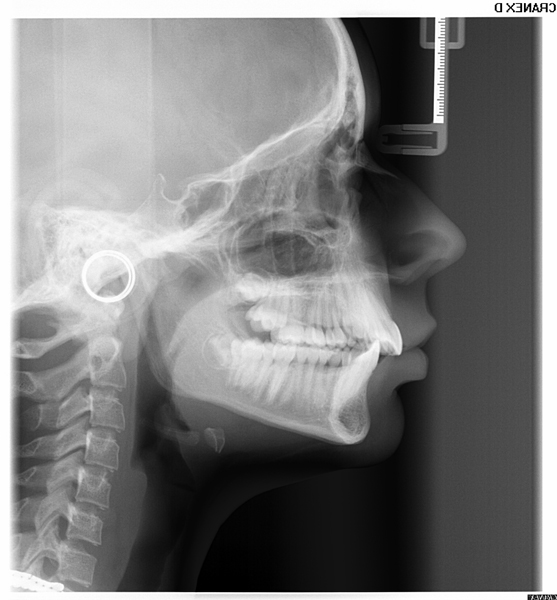

Telerradiografia Lateral

É uma radiografia lateral de crânio com uma distancia foco-filme maior e fixa de 1,5m , além disso utiliza-se os cefalostatos para posicionar o paciente de forma que seja possível a reprodutibilidade futura da mesma posição e seja possível fazer medições em ângulos formados por planos e linha. Nesta incidência são realizadas análises cefalométricas onde avalia-se o padrão dento-esqueletico- facial e o crescimento do crânio e da face.